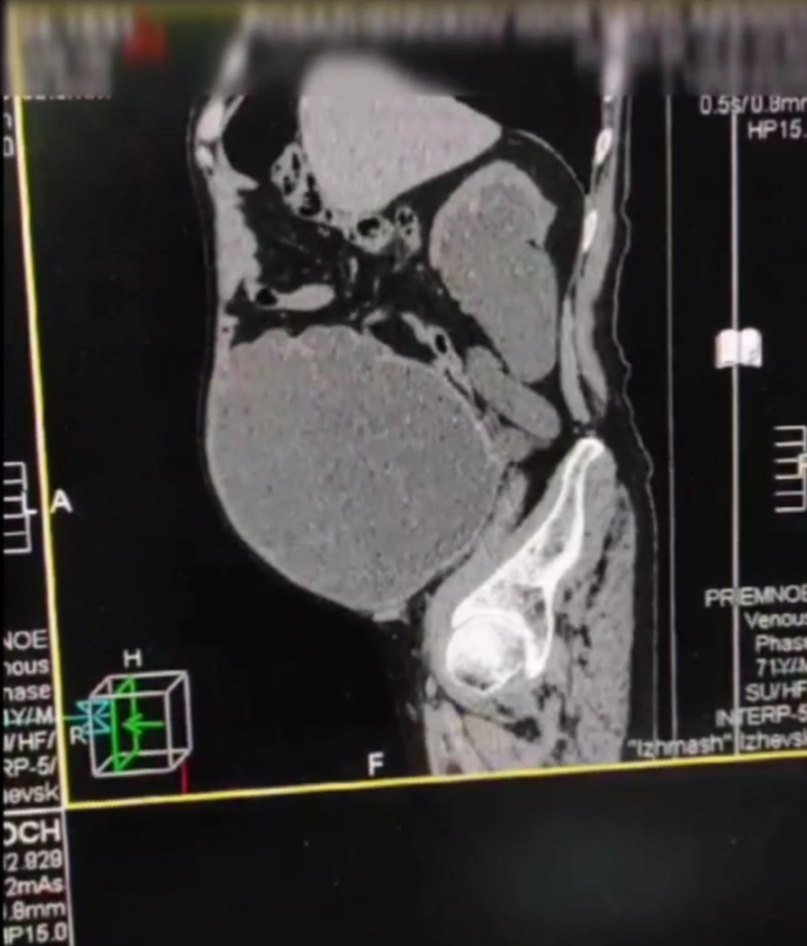

У пациента сформировался дивертикул мочевого пузыря. Ижевск, Удмуртия.

Дивертикул мочевого пузыря сформировался у пациента за несколько лет. Невнимательность к своему здоровью довела человека до опасного состояния. В мочевом пузыре начала скапливаться моча, а необходимость постоянного натуживания спровоцировала постепенное ослабление и растяжение стенки органа.

В результате мочевой пузырь занял большую часть брюшной полости. Врачи урологического отделения ГКБ №6 поставили уретральный катетер и вывели 9 литров мочи. Затем была установлена цистома.